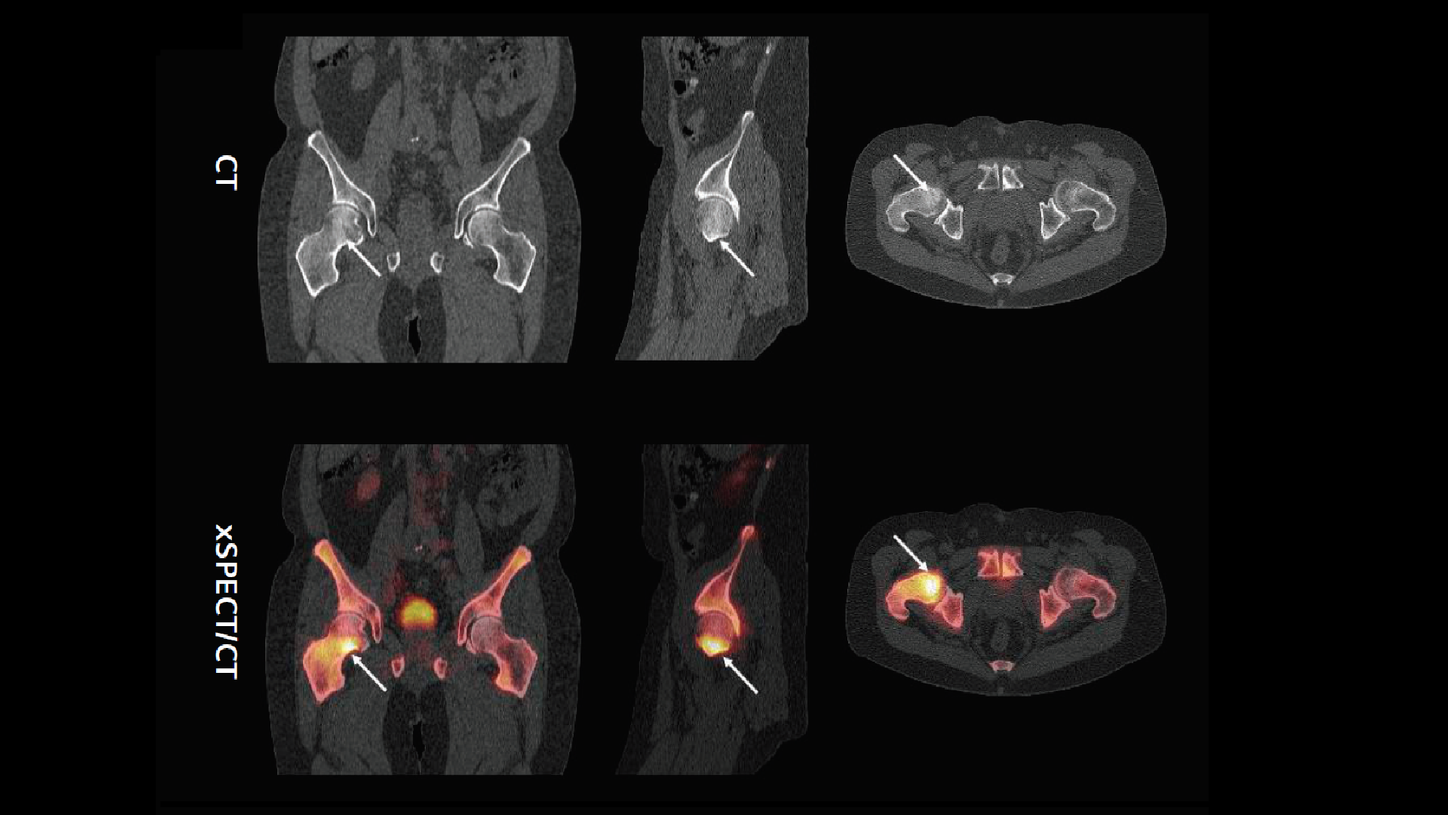

xSPECT Bone sharply defines the focal area of increased uptake in the medial margin of the neck of the femur adjacent to the femoral head. The rest of the femoral neck and the intertrochanteric crest also show slightly increased uptake. The femoral head uptake appears normal. Compared to SPECT (AC), the xSPECT Bone images show sharper margins of the hypermetabolic foci in the femoral neck as well as sharper delineation of the femoral head, trochanteric regions, intertrochanteric crest, and the rest of the pelvis and acetabulum.

CT shows mild sclerosis involving the femoral neck just adjacent to the femoral head, predominantly in the anterior and inferior aspect of the neck. Fusion of CT with xSPECT Bone shows exact coregistration of the focal increase in uptake with the zone of sclerosis. The correlation of the focal area of skeletal hypermetabolism, along with the associated sclerosis seen on CT in view of the MRI findings at the same area, strongly suggest the presence of lymphomatous infiltration in the marrow of the femoral neck.

xSPECT Bone sharply defines the extent of marrow infiltration in the femoral neck by lymphoma and correlates it with the degree and extent of sclerosis seen on CT. The well-defined boundaries of the skeletal hypermetabolism defined by xSPECT Bone provides information about the degree of involvement of the marrow of the greater trochanter and upper part of the femoral shaft beyond the heavily infiltrated region in the lower part of the femoral neck, thereby illustrating the greater extent of lymphomatous infiltration than was estimated from the CT or SPECT only.